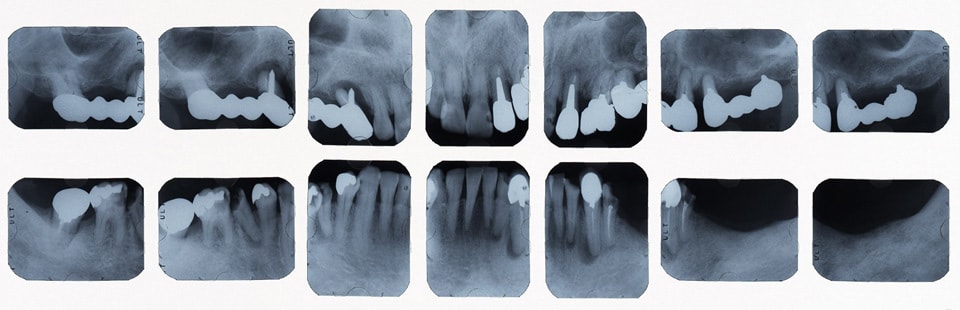

治療前レントゲン

奥歯をインプラントにて治療し、よく噛めるようにしました。また、虫歯や歯の根の治療のやり直しを行いセラミックにて審美的に修復しました。

どんな治療にもメリット・デメリットがあります。患者さんの年齢や口腔内の状態、さまざまな要因で、治療のメリット・デメリットの大きさは、変わってきます。患者さんの状態によって、受ける治療のメリット・デメリットは異なるので、治療を受ける際は、よく説明を受けられてからの方が、安心して治療を受けることが出来るかなと思います。

インプラントや入れ歯、ブリッジもそれぞれメリット・デメリットがあります。